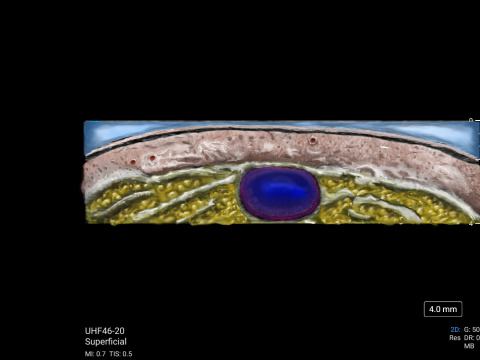

MSK Market Development Director, Daniel Shelton, shows off the capability of Sonosite UHF 46-20 with scans of a hair follicle and a vein. The scans were then illustrated to reveal details less obvious to the non-clinical eye.

Vein (small superficial branch), the cephalic on the distal 1/3 forearm